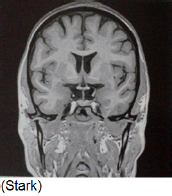

De acordo com a imagem a seguir, assinale a alternativa que determina a secção de corte.

A

Coronal.

B

Sagital.

C

Axial.

D

Látero-medial.

E

Oblíquo.